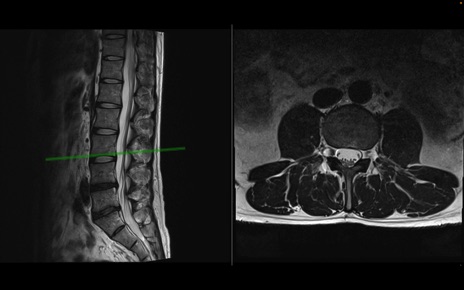

【整形】TIPS症例1 腰椎MRI 横断像と矢状断像

【症例】40歳代男性

【主訴】左臀部〜大腿後面痛み

【現病歴】2週間前から腰痛あり。2日前に夜中にくしゃみをした際に激痛が出現。疼痛強いため来院。

【身体所見】左臀部〜大腿後面、下腿後面のしびれ。SLR -/+ 30度、うつ伏せ困難、筋力低下なし。

異常所見と診断は?